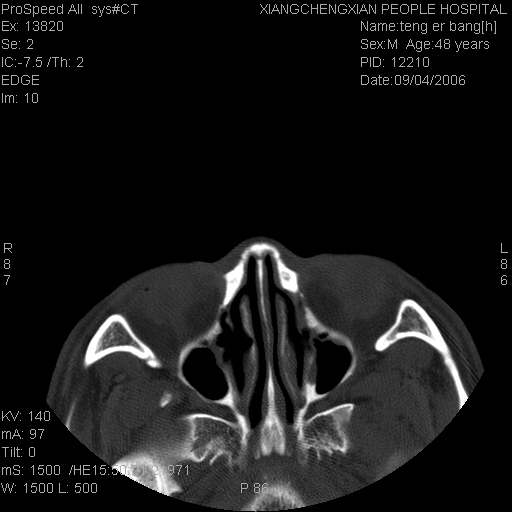

患者,男,以头面部外伤后头疼1小时为主诉入院,患者1小时前被他人打伤头部及左侧面部,眼睑无水肿,左侧面部肿胀压疼,未触及骨擦音。专科检查:耳鼻喉未见异常。

ct:平扫+冠扫:双侧鼻骨对比,冠扫s6#示右侧鼻骨尖部可见线状低密度影,边缘光滑,并见硬化.软组织未见肿胀.

诊断意见:鼻额缝(鼻骨与上颌骨额突缝),但个别同志认为是骨折.因此请同行们会诊.多谢了!

正常鼻颌缝。软组织无肿胀。鼻腔无积液积血。鼻骨光滑规整无中断。均不支持骨折。

正常的,双侧对称.边缘光整,且逢等宽.

正常鼻颌缝。软组织无肿胀。鼻腔无积液积血。鼻骨光滑规整双侧对称。均不支持骨折。